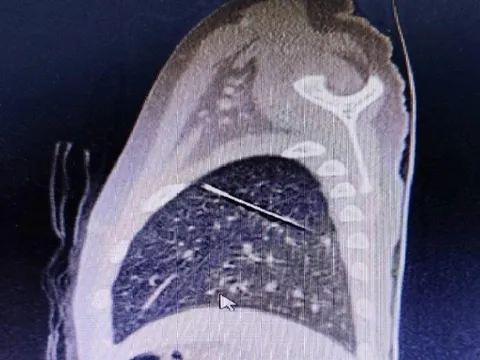

Hi hữu: Kim may quần áo đi lạc nằm sâu trong phổi bé 4 tuổi

Bé trai 3 tuổi thường qua tiệm may quần áo chơi nhưng không biết đã nuốt kim từ khi nào. Chỉ đến khi bé bị té gãy xương chân, bác sĩ kiểm tra mới phát hiện dị vật.